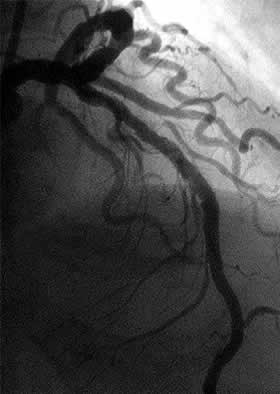

| Diagnosis: OMI (A), AP, CHF, SVD

Present Illness: '00.12.7 AMI (A) '01.8.10 CAG: #7 100%, #11,13 99% DCA for #11, 13 |

| Final CAG Findings:'01.10.9 LVG: asynergy (global), EF: 34% CAG: #7 100%, LCx no restenosis |

J-2 : 6 months follow-up angio